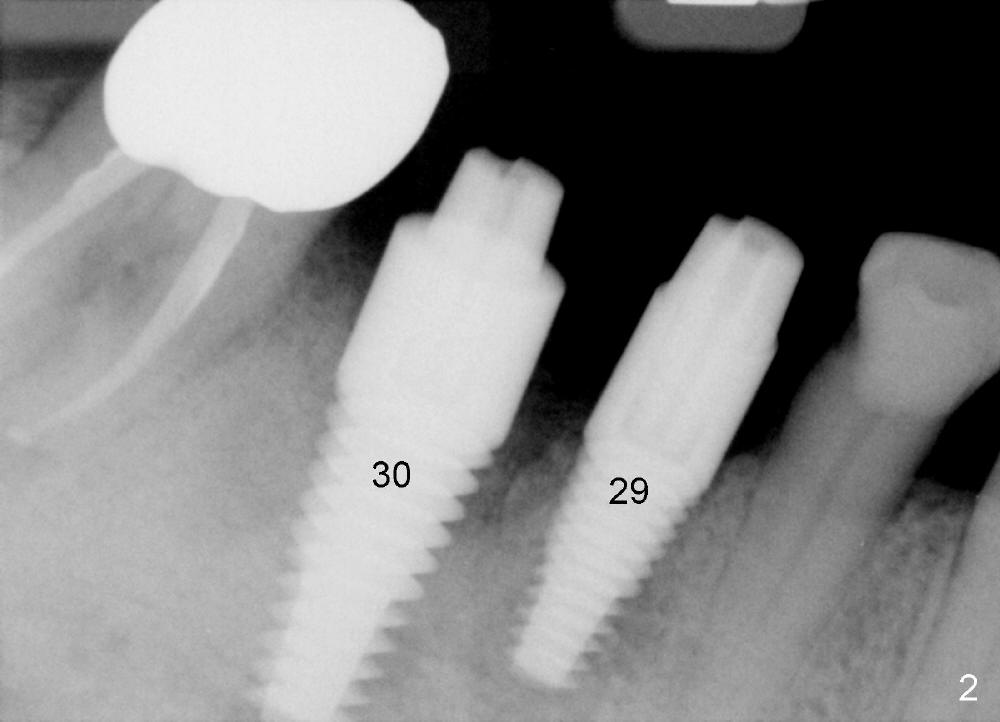

One month after implant placement at the sites of #29,30, the former is found loose (Fig.1,2). It is placed higher than #30. Three weeks later, PA is retaken to confirm that there is space apical to the implant at #29 (Fig.3 double arrows) and that there is distance from the mental loop (yellow dashed line). After infiltration anesthesia, the implant is torqued down initially (compare Fig.4,5) and more (Fig.6,7). To prevent re-loosening, the two implants are splinted (Fig.8).